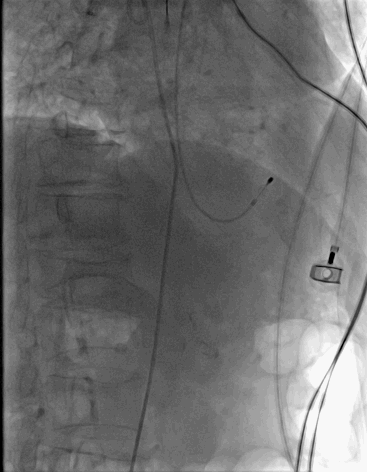

再行降主动脉造影见降主动脉穿透性溃疡。

TEVAR术前降主动脉造影

经右侧股动脉途径送入LifeTech Ankura 28*160mmm大动脉覆膜支架,支架远端定位于腹腔干开口上缘,准确定位后释放大血管支架。

再行降主动脉造影见主动脉支架贴壁良好,透壁溃疡完全隔绝,未见明显内漏,腹腔干开口未受影响,血流通畅。

TEVAR-主动脉覆膜支架植入后